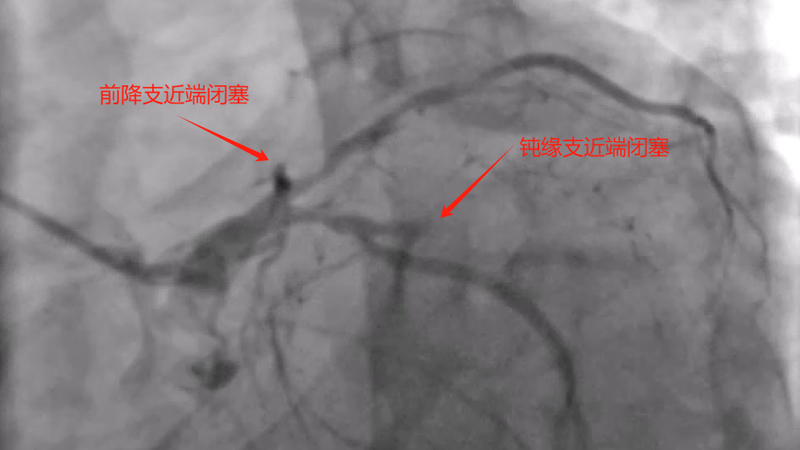

患者王某,男性,61岁,长期抽烟,本次因活动后气促入院,考虑冠心病导致心功能下降所致,经过治疗后,与家属及患者沟通后同意行冠状动脉造影。造影提示前降支、钝缘支及右冠均慢性闭塞,可见小血管侧支循环闭塞血管,冠脉病变极为复杂,获得家属同意后,来凤县人民医院心血管内科介入团队为患者制定了手术方案,先尝试开通右冠闭塞血管,择期尝试开通前降支闭塞及钝缘支闭塞血管。经过接近3小时努力,成功开通患者右冠闭塞血管,并联合IVUS成功植入支架,患者右冠血流恢复正常。

术前